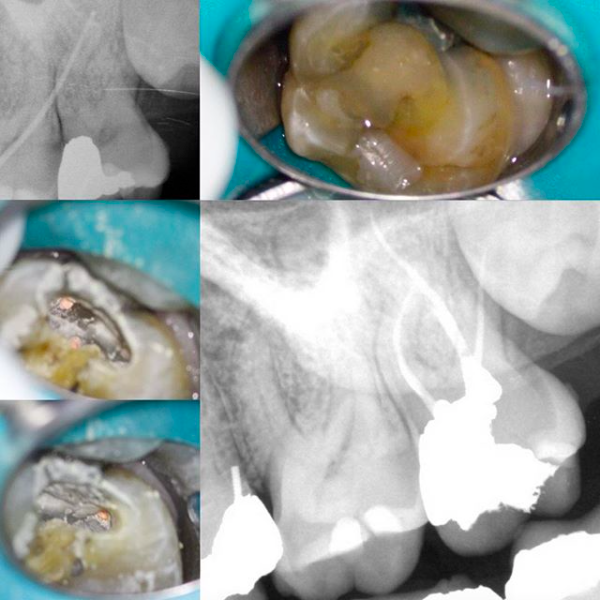

There it is, 1st post on TDO University. 2.7 Necrotic/CAA. Small mouth + limited opening. 2 visits + Ca(OH)2. Sinus tract healed after 1st visit. Vortex Blue 25/.04. Amalgam core. Left thin mesial wall of old amalgam that will be removed during crown prep to act as a matrix to help packing new amalgam core. I want to thank all TDO members and TDO University members for contributing. Keep on learning!